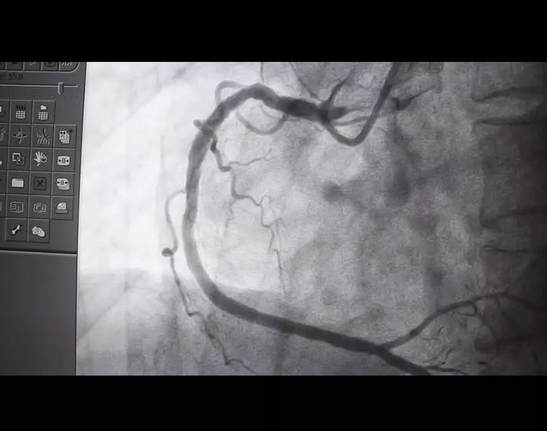

杨先生到达医院后,经进一步检查,确诊为急性心肌梗死。征得家属同意后,医生立即为杨先生实施手术。

医生 王楚林:持续的胸痛,心电图表现也是急性心肌梗死,到我们医院很快就进行PCI治疗,把心梗的血管开通。